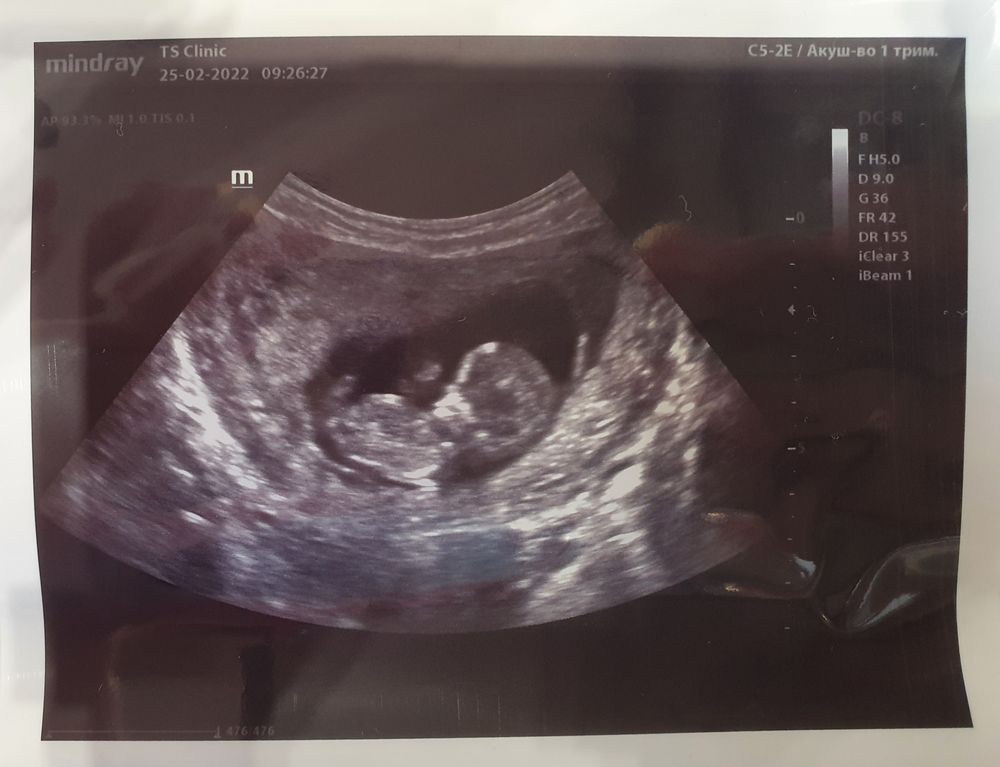

Девчонки, посмотрите пожалуйста кто разбирается♥️ 🙌🏻 Я ничего не понимаю и не вижу ) срок 12 и 3

На фото бугорка не видно, так что пол не предположить. Но по лобику на мальчика похож)